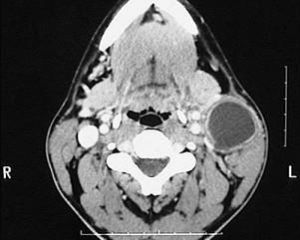

鰓裂囊腫不僅可以準確定位,而且對病變的範圍、大小、是否合併感染等都能準確診斷。鰓裂囊腫通常表現為沿胸鎖乳突肌上、下走行,類圓形或橢圓形軟組織塊影,中心密度低,不強化,但囊壁(邊緣)可強化,境界清楚。若病變位於頸前三角區,第二鰓裂囊腫最多見。若囊壁增厚,邊緣不光滑,強化掃描可見囊壁明顯強化,與周圍組織結構分界不清晰,囊內容物密度增高,提示囊腫有感染。